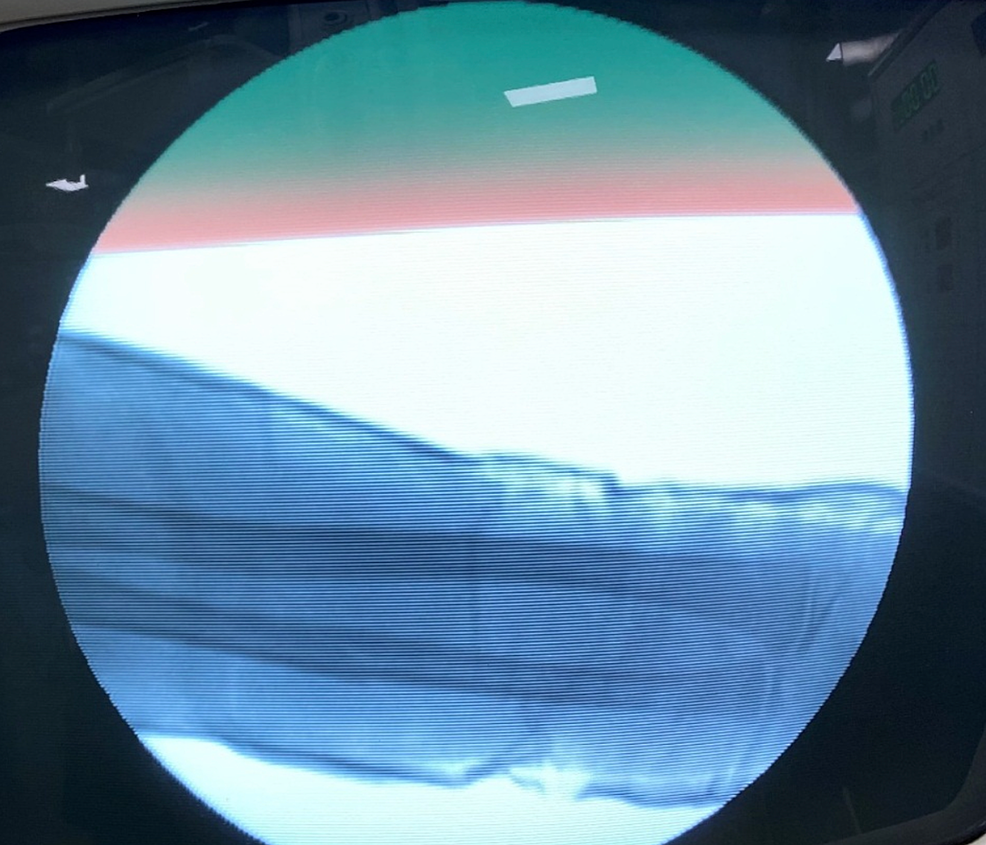

Pre-operative antero-posterior (AP) and lateral x-ray were taken (Figure 1). Adequate sedation was given to the patient. Fracture was reduced by the standard technique of axial traction manipulation. Reduction was confirmed radiologically by image intensifier and if found satisfactory, cast application was done (Figures 2, 3).

The above-elbow cast was put after proper padding, with elbow joint in extension and forearm in the most stable position (Figure 4). A cast index = 0.7 or less, calculation of which was done by dividing inner sagittal width of cast by inner coronal width of cast at fracture level, decreases fracture re-displacement risk. If reduction was not found to be acceptable, the process was repeated under general anesthesia with the help of a C-arm.